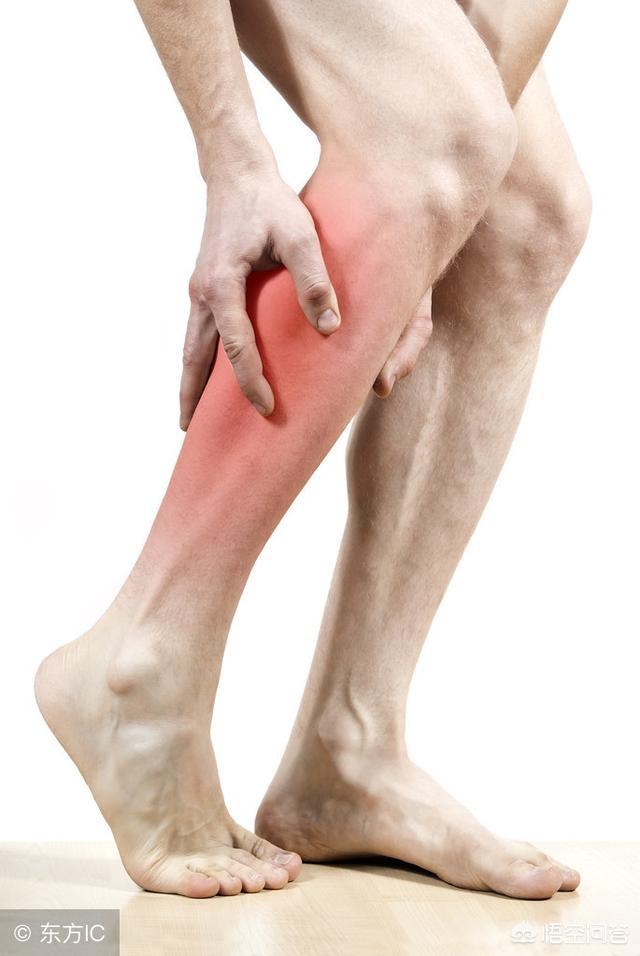

Hernie discale lombaire : douleur irradiant de la région lombo-sacrée vers les membres inférieurs le long du nerf sciatique, accompagnée d'un engourdissement des membres et d'une claudication intermittente dans les cas graves. Le point de pression est souvent situé au milieu du dos. La douleur est généralement vague.

Outre les douleurs lombaires, la hernie discale lombaire est également susceptible d'entraîner des douleurs dans les jambes en raison de l'atteinte du nerf sciatique.Sa douleur présente plusieurs caractéristiques :

- En général, la lombalgie survient avant la douleur dans les jambes, et les deux peuvent se produire en même temps ;

- Les points de pression adjacents à l'apophyse épineuse affectée sont limités à l'endroit de la hernie discale ;

- La douleur irradie de la région lombaire le long du nerf sciatique vers le mollet latéral, le dos du pied ou les orteils, et si la racine du nerf lombaire 4 est comprimée, elle produit également une douleur irradiant vers la partie antérieure de la cuisse ;

- Les symptômes douloureux sont exacerbés lors de la toux, des éternuements et de la défécation en raison de l'augmentation de la pression du liquide céphalo-rachidien ;

- La douleur est intense pendant l'activité et s'atténue au repos. Les symptômes ont tendance à s'aggraver lorsque le bas du dos est exposé au froid et à l'humidité ;

- Outre la douleur, l'engourdissement et les douleurs dans le bas du dos et les jambes sont des symptômes courants.

Il s'agit d'une douleur à l'arrière de la face externe des fesses et des cuisses, à la face externe des mollets qui s'étend parfois jusqu'aux talons, et la douleur est généralement aggravée lorsque l'on éternue ou que l'on tousse.